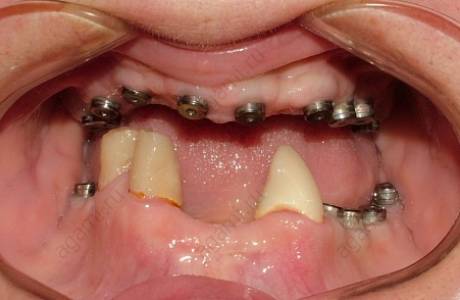

До лечения

Пациентка обратилась с жалобами на отсутствие жевательных зубов на нижней челюсти, неудовлетворительный внешний вид ранее изготовленных конструкции.

При остмотре также выявлено занижение высоты нижнего отдела лица и полное отсутствие прикуса, при том, что у пациентки изначально был патологический прикус с глубоким резцовым перекрытием.

Принято решение провести тотальную реабилитацию прикуса, восстановление эстетики и высоты нижнего отдела лица.